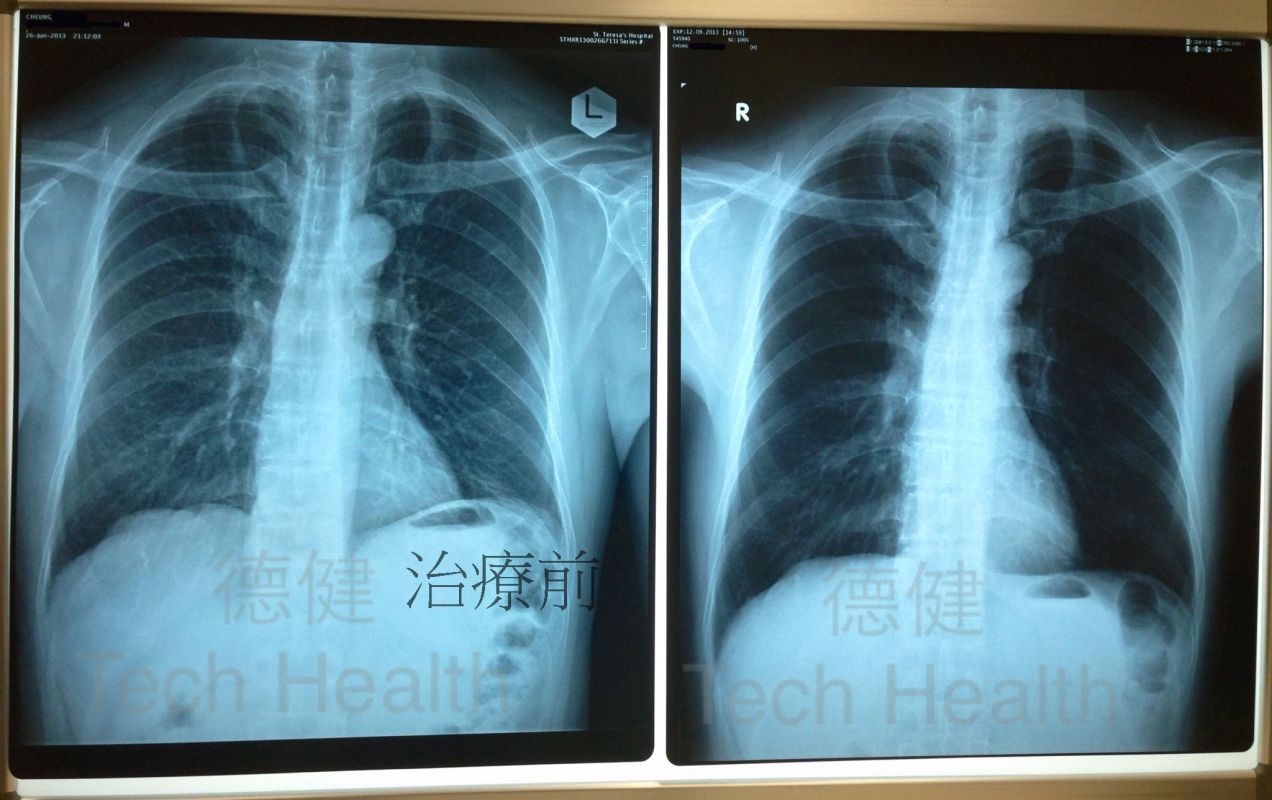

個案七 - 張先生 63歲 - 肺部纖維化,引致患者呼吸困難。

1.從X光片檢查發現患者肺部纖維化,引致患者呼吸困難,上落樓梯氣喘更甚,全身乏力,雙腳水腫,兼有痛症,早泳習慣亦因而停止。

患者經過45次經穴激活系統療法的組合治療後,所有不適症狀均已消除,從覆檢的X光片中,可見肺部組織纖維化部份有95%以上回復正常,而患者亦已回復正常生活,且生活質素良好。